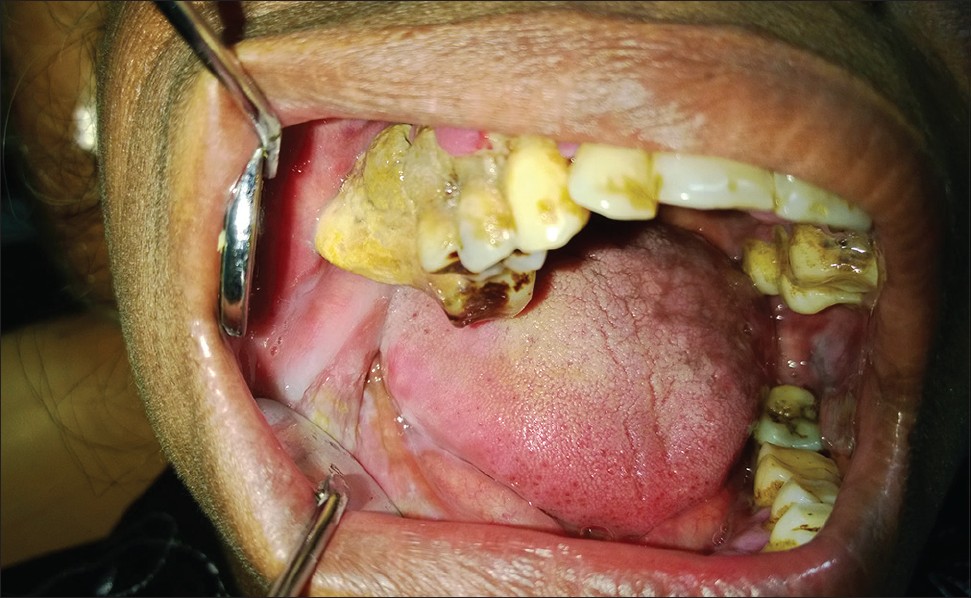

Giant calculus |

p. 174 |

Treville Pereira, Subraj Shetty, Svylvy Pereira DOI:10.4103/2278-9626.134857 |